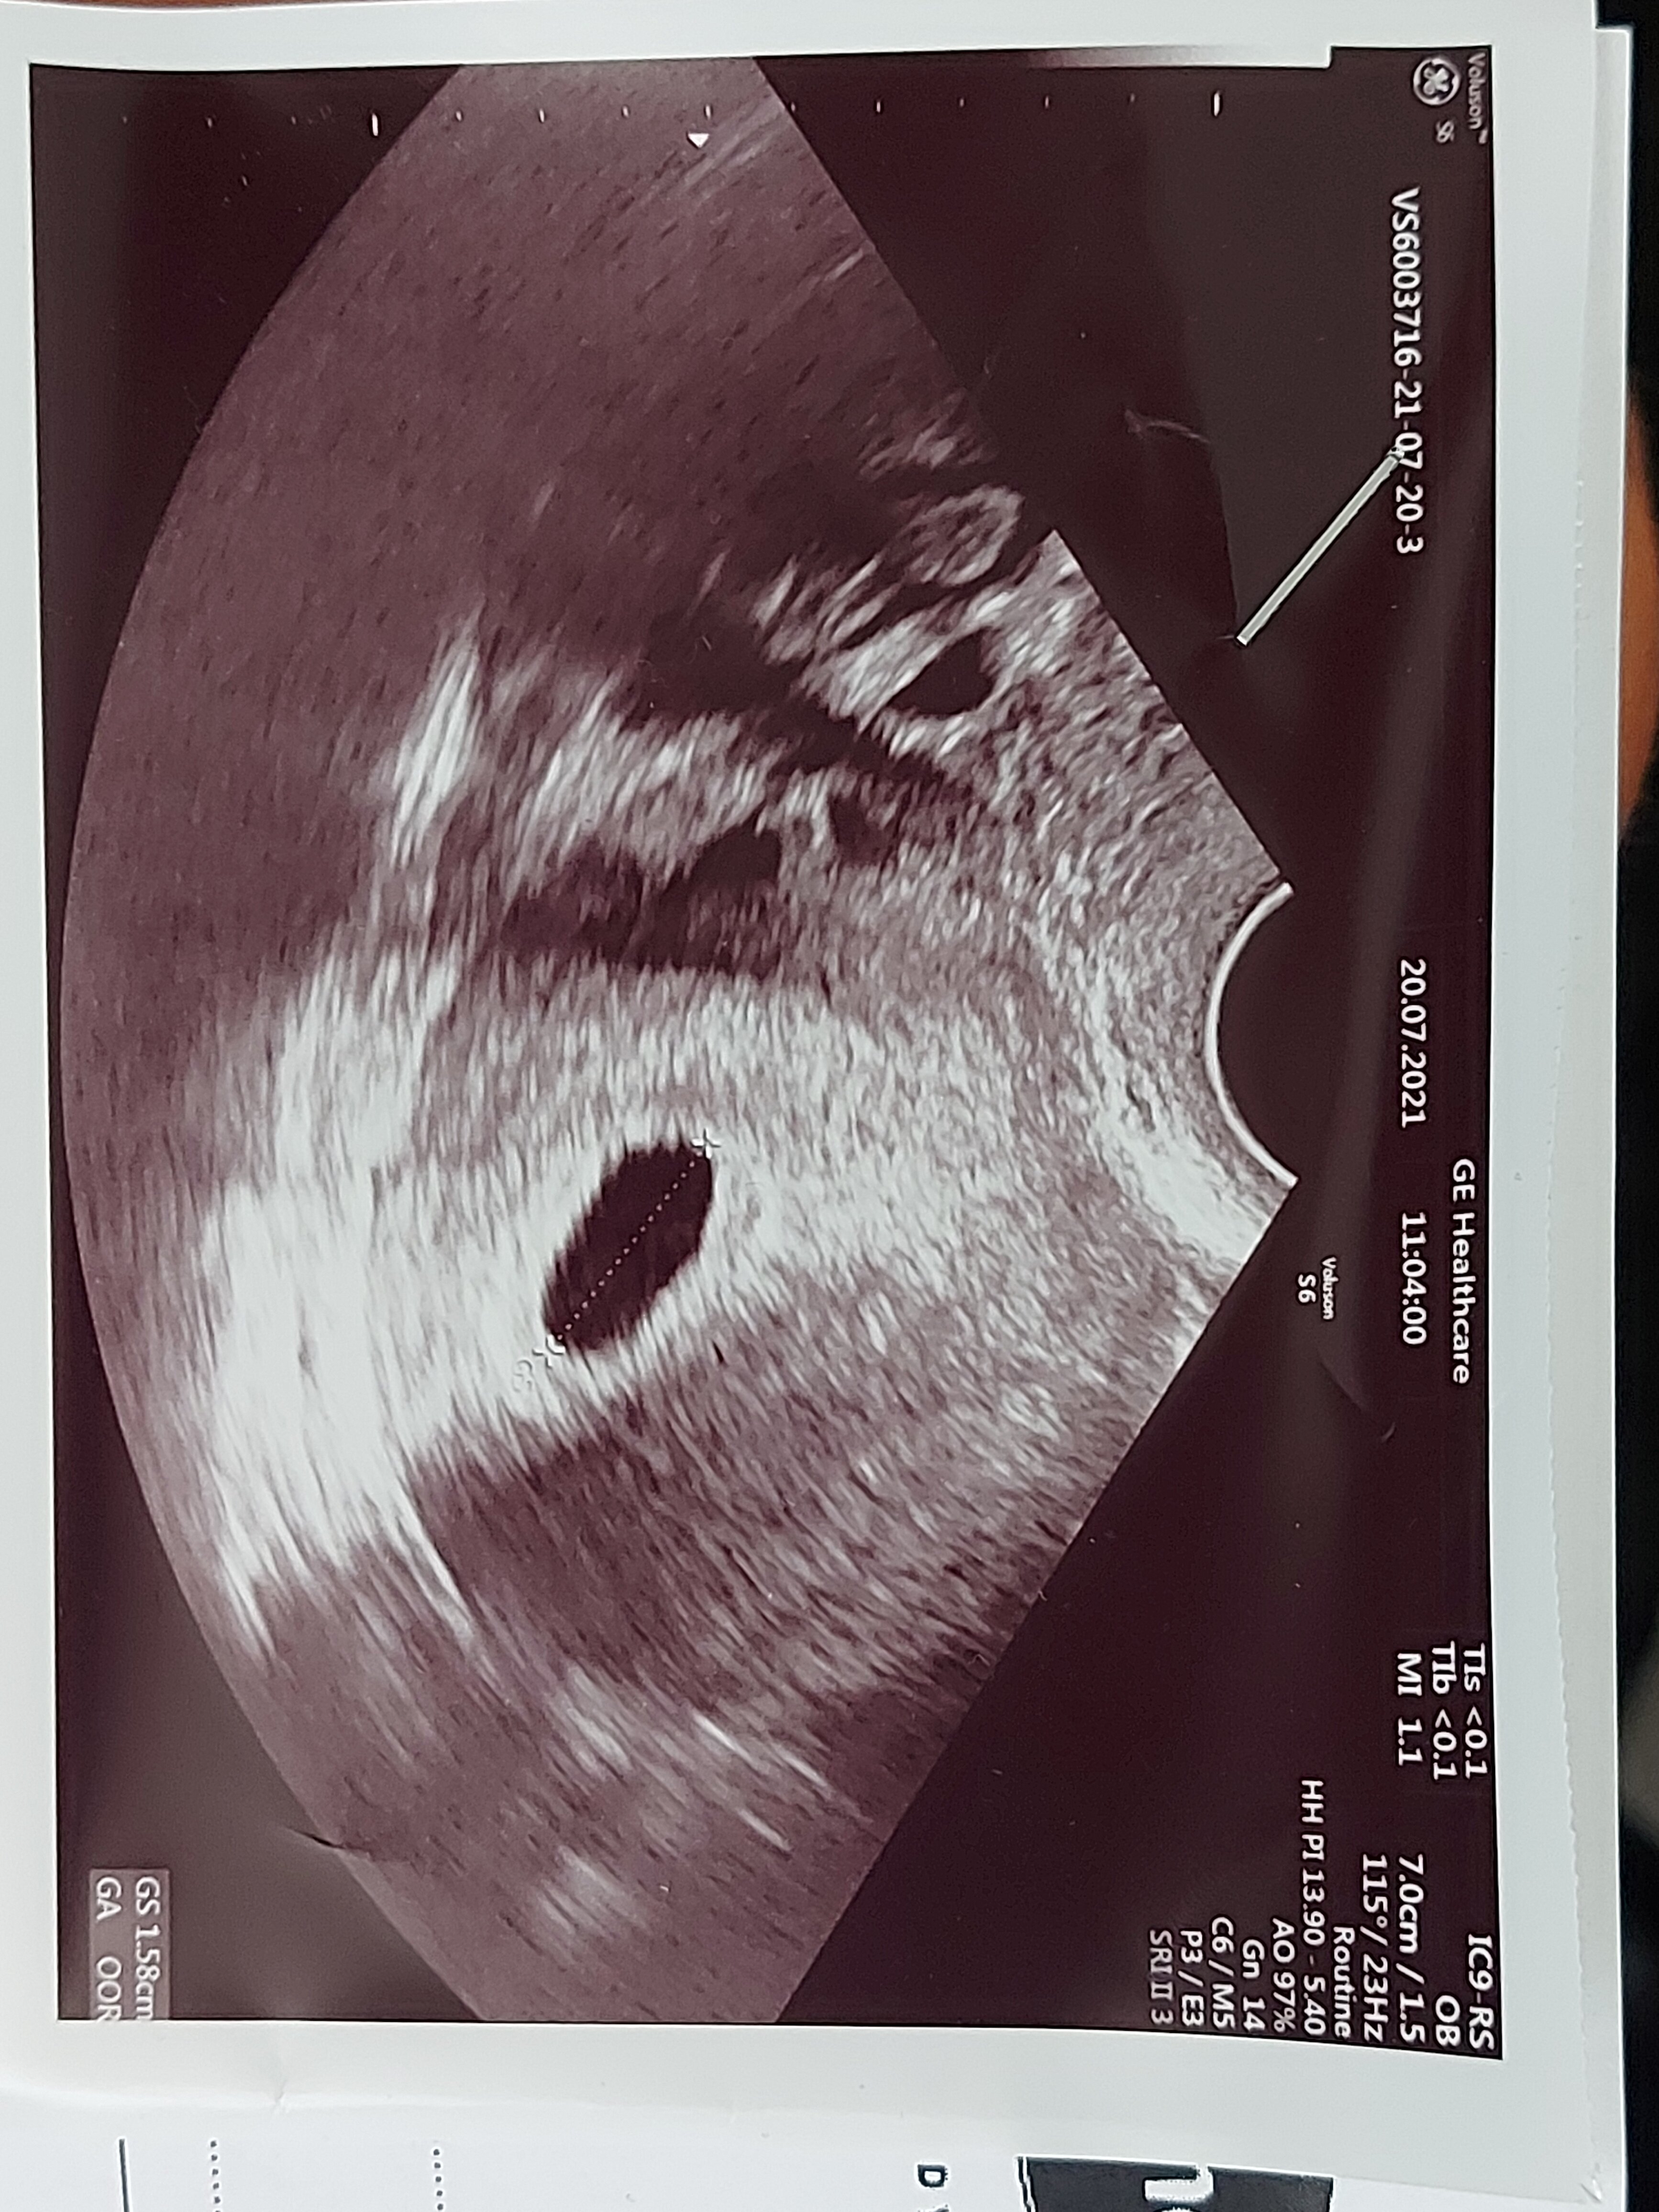

Czesc jestem w 6tc i po ostatniej wizycie pani doktor która najpierw mnie skomentowała ze w krótkich spodenkach się nie przychodzi do lekarza bo ona czuje się obrazona pierwszy raz się z czym takim spotkalam zdenerwowana przebadała mnie i mówi ze tu coś jest nie tak bo nie ma serca ani głowy ze chyba bezczaszkowiec I ona się pod tym nie podpisze i dala mi skierowanie do szpitala na szczegółowe badanie USG ( na skierowaniu napisala niewyraźny obraz usg chyba ciąża obumarla)Poszlam ale p.doktor powiedzial ze dopiero za tydzień możemy zobaczyć czy wszystko ok bo to wczesna ciąża.Chce jeszcze dodać ze tydzień temu bylam prywatnie i lekarz na usg powiedział ze widzi sam pęcherzyk.Co Wy o tym myślicie i uważacie bo jestem bardzo zdenerwowana szczegółowe badanie bede miec 4sierpnia.Jestem załamana.Ilona 40lat druga ciąża.

• 20210721_092442.jpg

20210721_092442.jpg

1,3 MB · Wyświetleń: 249

Dzis bylam prywatnie n usg niestety ciąża obumarła nie ma serduszka :(

Dzis bylam na usg prywatnie niestety ciąża obumarła 😢